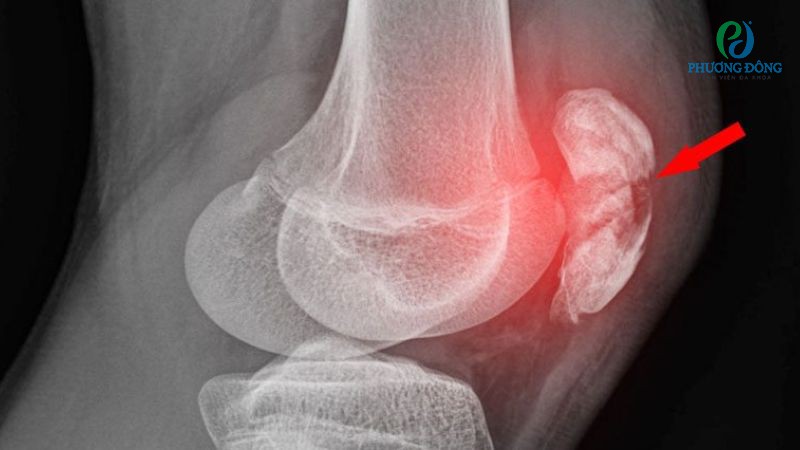

Chấn thương xương bánh chè

Chấn thương xương bánh chè xảy ra chủ yếu xảy ra do khớp gối phải chịu áp lực lặp lại, va chạm mạnh hoặc kỹ thuật sai tư thế khi chơi bóng rổ. Trường hợp này đòi hỏi can thiệp điều trị trong thời gian sớm nhất, áp dụng đúng phương pháp để đẩy nhanh tốc đồ liền xương và hồi phục chức năng vận động.

Chấn thương xương bánh chè khi chơi bóng rổ